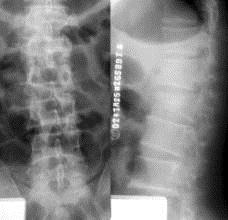

病历摘要: 患者×××,男性,21岁,不慎从3米高处坠落,双足着地,出现双足跟肿胀疼痛,腰痛不能站立。查体:腰1棘突有压痛和叩击痛,双足足跟部肿胀,触痛(...

问题 病历摘要: 患者×××,男性,21岁,不慎从3米高处坠落,双足着地,出现双足跟肿胀疼痛,腰痛不能站立。查体:腰1棘突有压痛和叩击痛,双足足跟部肿胀,触痛(+),双下肢感觉正常,双足伸足母、伸趾正常,双膝关节伸屈正常。 为了明确诊断需要做哪些检查?

选项 A、穿刺活检 B、抽血测ESR、C-反应蛋白 C、腰椎MRI D、全身骨扫描 E、腰椎X线片 F、腰椎CT G、双足X线片

答案 CEFG